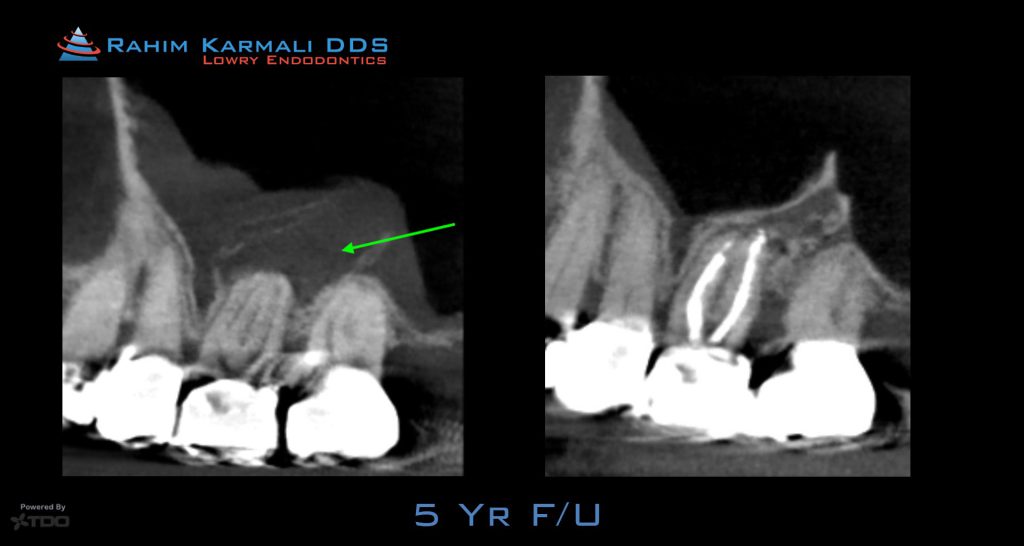

This patient had a severe root canal infection that invaded her sinus. Careful treatment with laser disinfection was performed. At the 5 year follow up, her symptoms were gone, the sinus floor re-established and her maxilla regenerated.